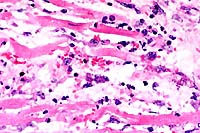

- In sections of both lobes of the thyroid gland, follicles

are small and lack colloid. Follicular epithelial cells are columnar

to polygonal and occasionally bilayered. The cytoplasm is eosinophilic,

abundant, and contains large, clear, poorly defined vacuoles.

Basal to central nuclei are large (up to 15 mm in diameter),

round and have coarsely stippled chromatin.

10x

obj

- Case14-1. Thyroid. There is diffuse follicular epithelial

hypertrophy and hyperplasia. Relatively few follicles have discernable

lumens or colloid production.

40x

- Case14-1. Thyroid. Follicular epithelium is hypertrophic

and vacuolated. Follicle colloid is globular and sparce.